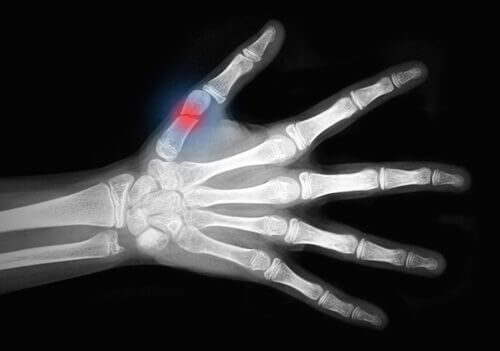

Остеопороз послаблює кістки, роблячи їх крихкими та схильними до переломів. Зап’ястя, стегна, хребет – це ділянки найбільшого ризику.

Через слабкі кістки, вони здатні легко ламатися. Не важливо чи це було падіння, чи удар.